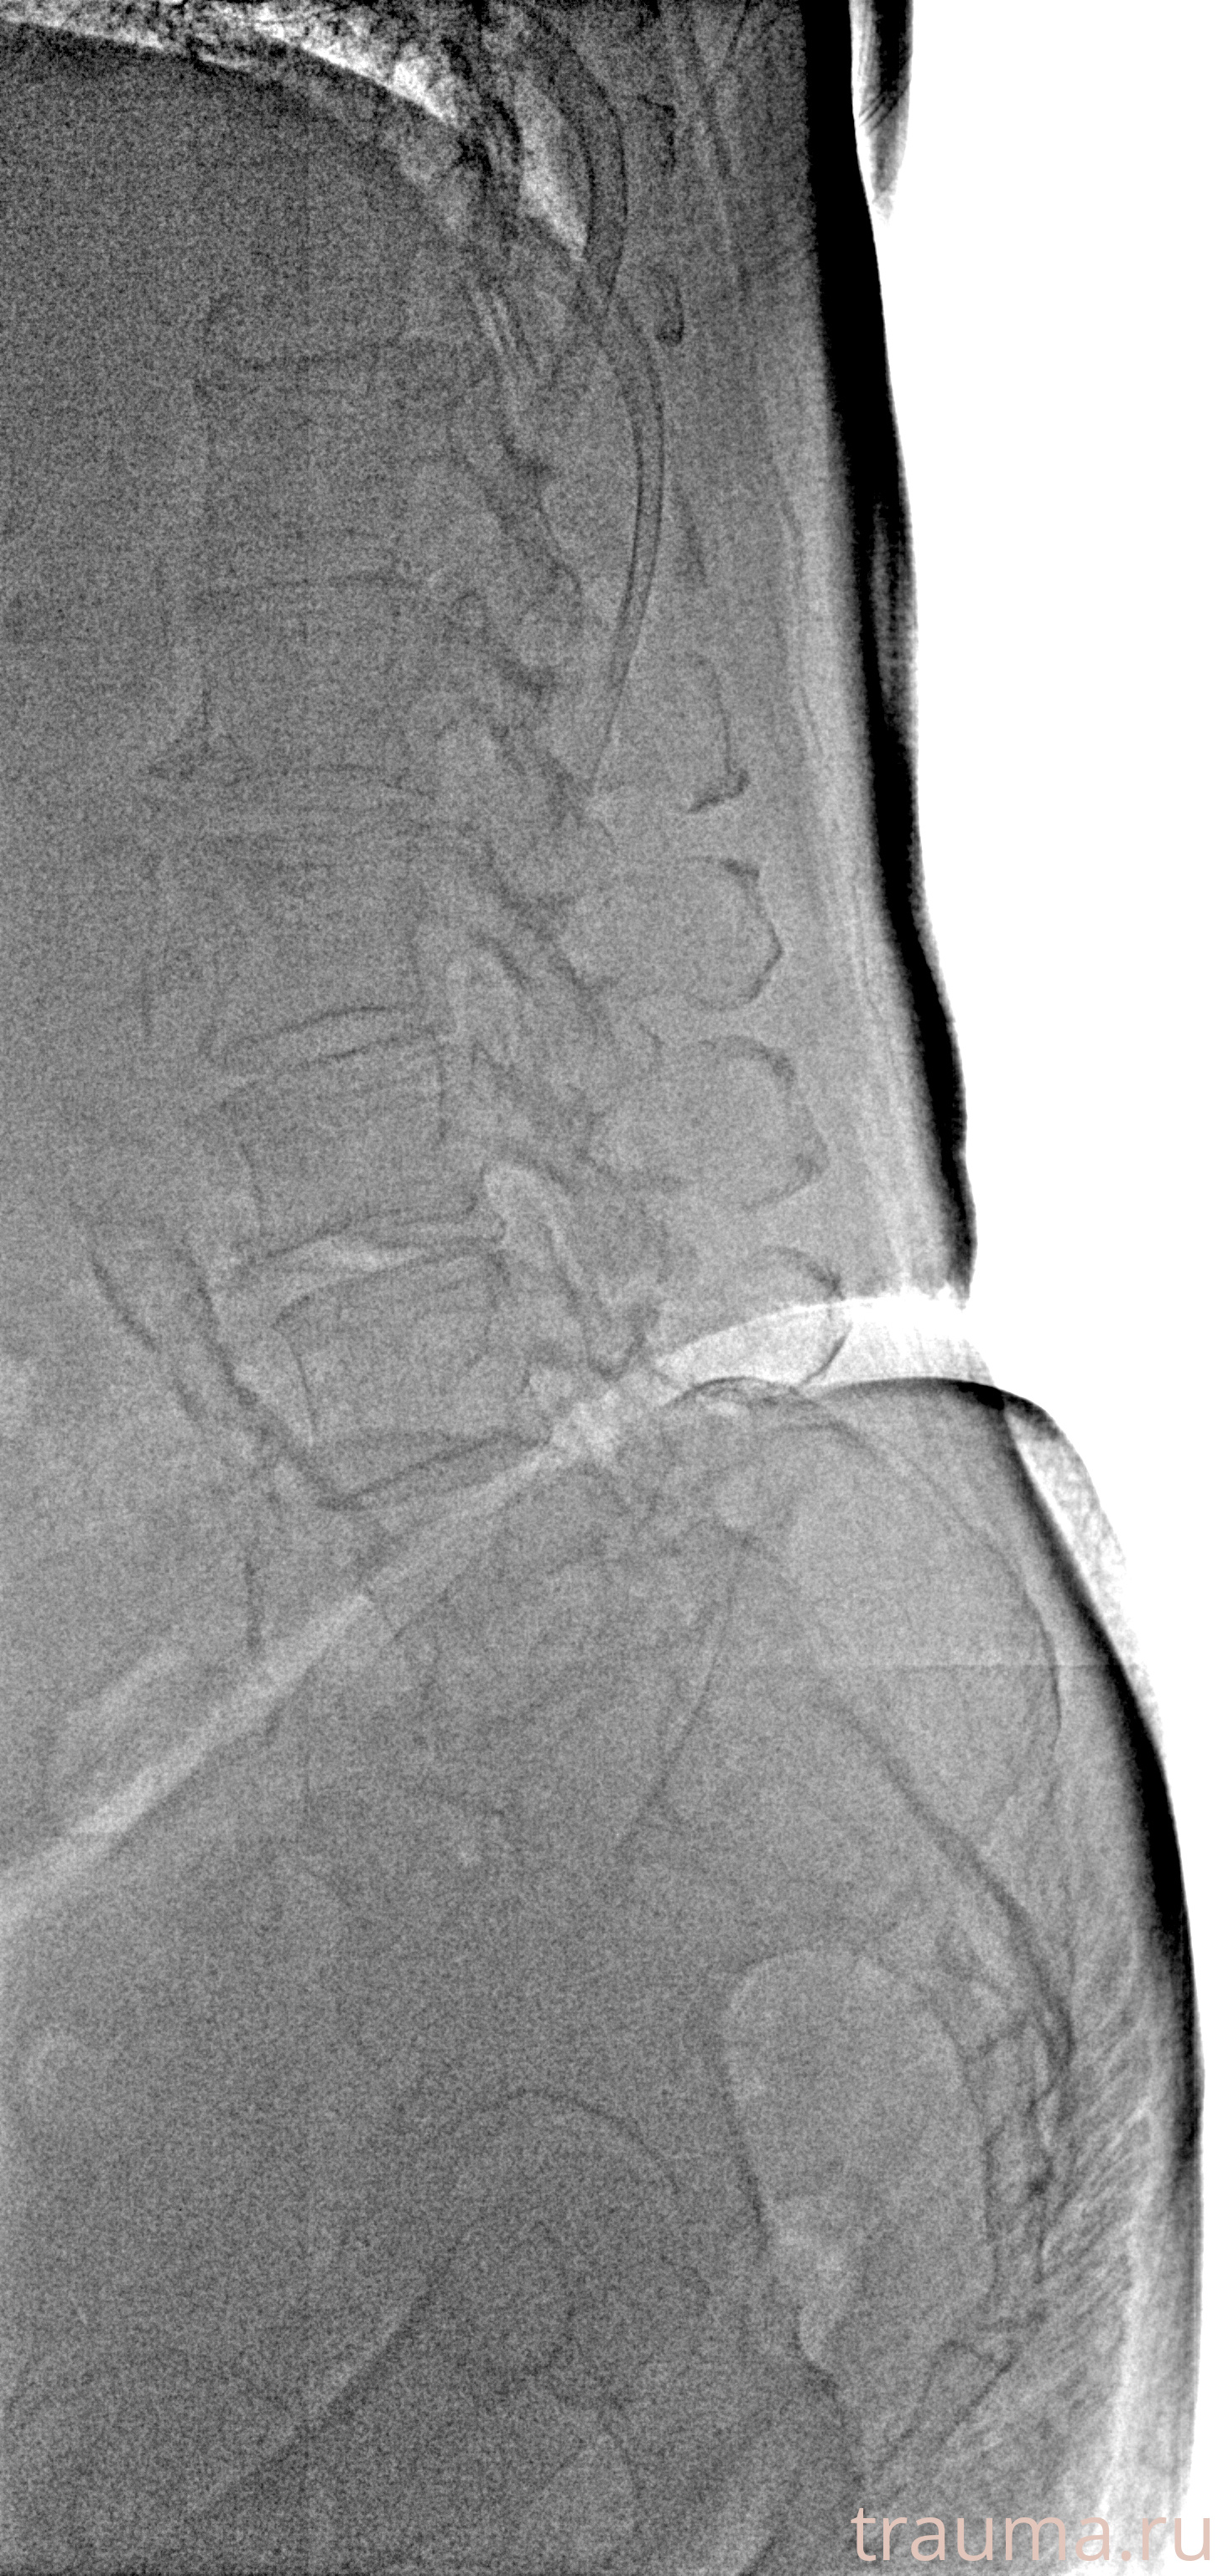

Рентгенограммы

Рентген на дому: по вашему адресу приезжает врач-рентгенолог, травматолог-ортопед с мобильным рентгеновским аппаратом, проводит диагностику травмы или заболевания, делает необходимые рентгенограммы, дает рекомендации по дальнейшему лечению. Получить качественные снимки в домашних условиях возможно благодаря уникальной методике, разработанной МосРентген Центром для института  Склифосовского